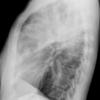

different case

Round pneumonia

Date: 11/28/2009

Views: 5931